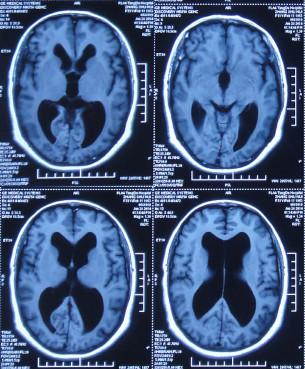

患者2014年6月20日出现持续头晕的症状,不能自行缓解,于2014年6月24日和6月26日分别就诊于甘肃省平凉县某医院和陕西省西安某医院,进行了头颅MRI和头颅CT示脑室扩张,脑积水(图-1、图-2)。

图-1:2014年6月24日头颅MRI

为治疗脑积水,于头晕发病8天后即2014年6月28日,就诊于陕西省西安某三甲医院神经外科,当天查头颅MRI:脑积水(图-3)。

图-3:2014年6月28日头颅MRI